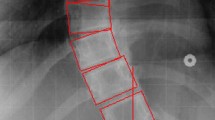

Radiographic features used for computer assisted classification of scoliosis are medial axis and CSL. It requires 70 landmark identification at the corners of 17 vertebral body starting from T1 to L5. The proposed computerised image understanding system automatically defines medial axis and CSL with the help of image processing techniques. Medial axis is embedded within the vertebral column. Different thresholding techniques are applied to select proper ROI from the posterioanterior radiographs. The resultant vertebral columns are shown in Fig. 6b. Determination of medial axis needs only the boundary coordinates. These boundary coordinates are retained using boundary descriptors as shown in Fig. 6c. Coordinates of the spine axis are nothing but the average coordinates of the boundary in X- axis. CSL is nothing but the vertical line drawn from the center point of the L5 vertebra. Figure 6d shows the medial axis and mid line for the classification procedure.